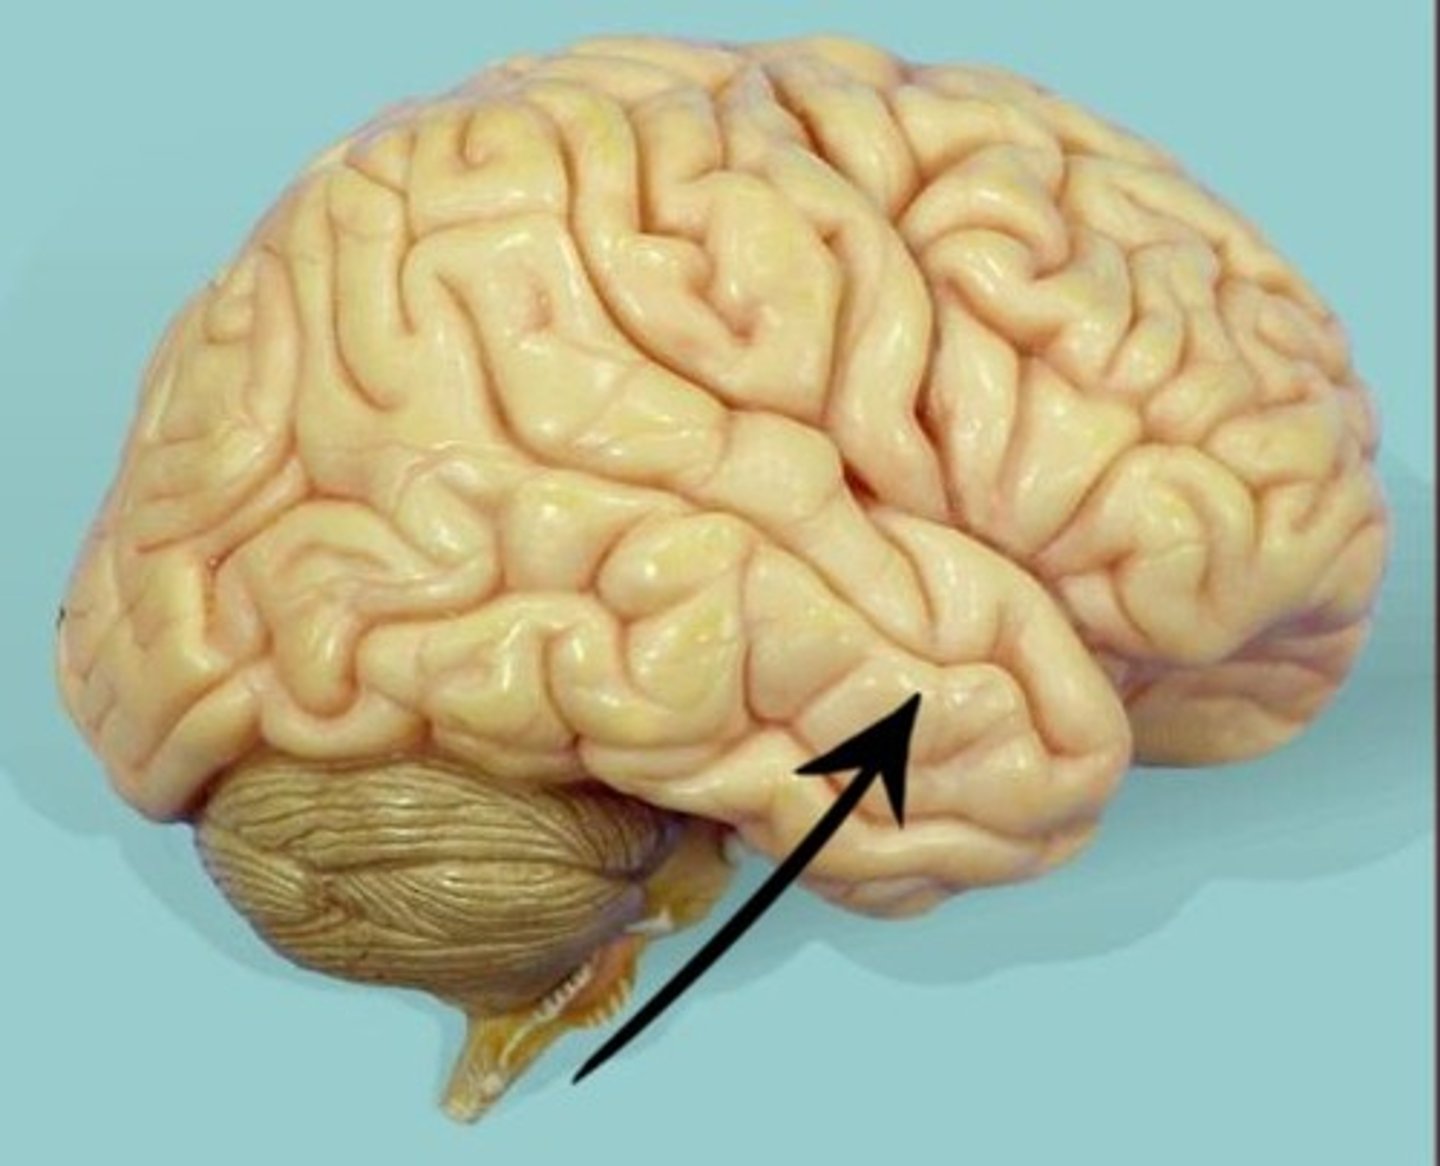

temporal lobe